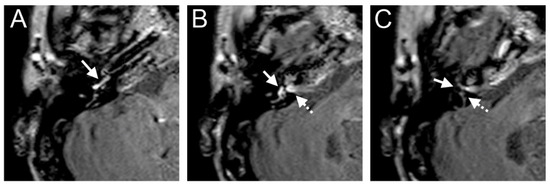

A 60-year-old male presented with a sudden hearing loss on the right side for one week. The PTA was 110 dB on the right side. The patient had already had a sudden hearing loss on the same side in history, which was recovered. He denied having any other symptoms, such as tinnitus, vertigo, or aural fullness. He already had a cochlear implant on the left side related to sensorineural hearing loss. The visual examination showed a spontaneous nystagmus to the left side. A right-side hyporeflexia was observed in the caloric test. The VHIT test revealed a decreased right anterior (0.00) VOR gain. Intraoperatively, a PLF track around the RW niche was observed. The CTP test on the right side was positive, suggesting a PLF. On the 4 h delayed 3D-FLAIR image, a cochlear and vestibular contrast enhancement on the side of hearing loss was found (Figure 1). However, about 3/3 of fluid filling in the RW niche was observed in the affected ear in the CT, which could not be confirmed on T2W MRI. Additionally, the mesotympanon, hypotympanon, and mastoid were filled with fluid on the CT. Because of artifacts on the left side after CI, a side-to-side comparison was not possible.

Figure 1. A 60-year-old male presented with a sudden hearing loss on the right side for one week. The axial 4 h delayed 3D FLAIR sequence shows a contrast enhancement in the cochlear basal turn (arrow) (A) and vestibulum (B). About 3/3 of fluid filling in the RW niche was observed (arrow, (C)).